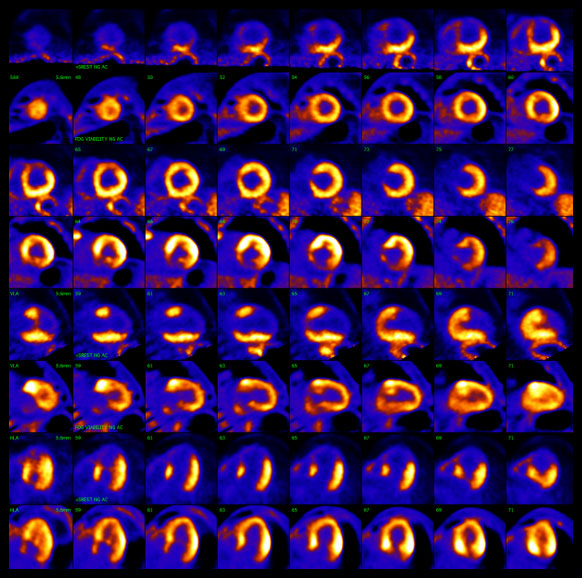

Cardiac Pet/ct

Enhance your business with our stunning commercial Cardiac Pet/ct collection of numerous professional images. optimized for commercial use with truck, vehicle, and automobile. ideal for corporate communications and branding. Discover high-resolution Cardiac Pet/ct images optimized for various applications. Suitable for various applications including web design, social media, personal projects, and digital content creation All Cardiac Pet/ct images are available in high resolution with professional-grade quality, optimized for both digital and print applications, and include comprehensive metadata for easy organization and usage. Discover the perfect Cardiac Pet/ct images to enhance your visual communication needs. Our Cardiac Pet/ct database continuously expands with fresh, relevant content from skilled photographers. Reliable customer support ensures smooth experience throughout the Cardiac Pet/ct selection process. Professional licensing options accommodate both commercial and educational usage requirements. Multiple resolution options ensure optimal performance across different platforms and applications. Regular updates keep the Cardiac Pet/ct collection current with contemporary trends and styles. Each image in our Cardiac Pet/ct gallery undergoes rigorous quality assessment before inclusion. Time-saving browsing features help users locate ideal Cardiac Pet/ct images quickly. The Cardiac Pet/ct archive serves professionals, educators, and creatives across diverse industries. Comprehensive tagging systems facilitate quick discovery of relevant Cardiac Pet/ct content.